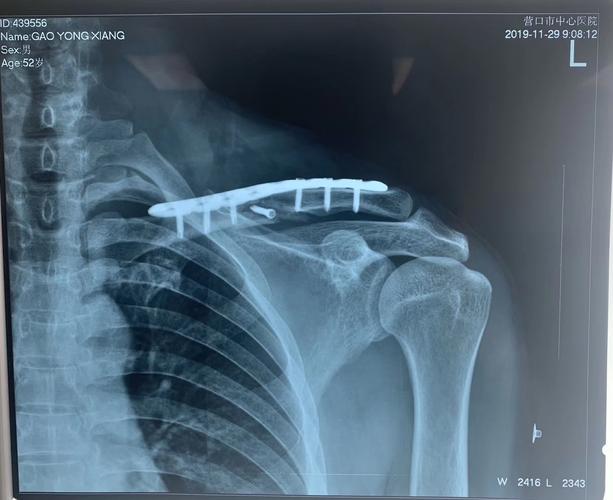

锁骨骨折微创治疗之mipo

锁骨骨折